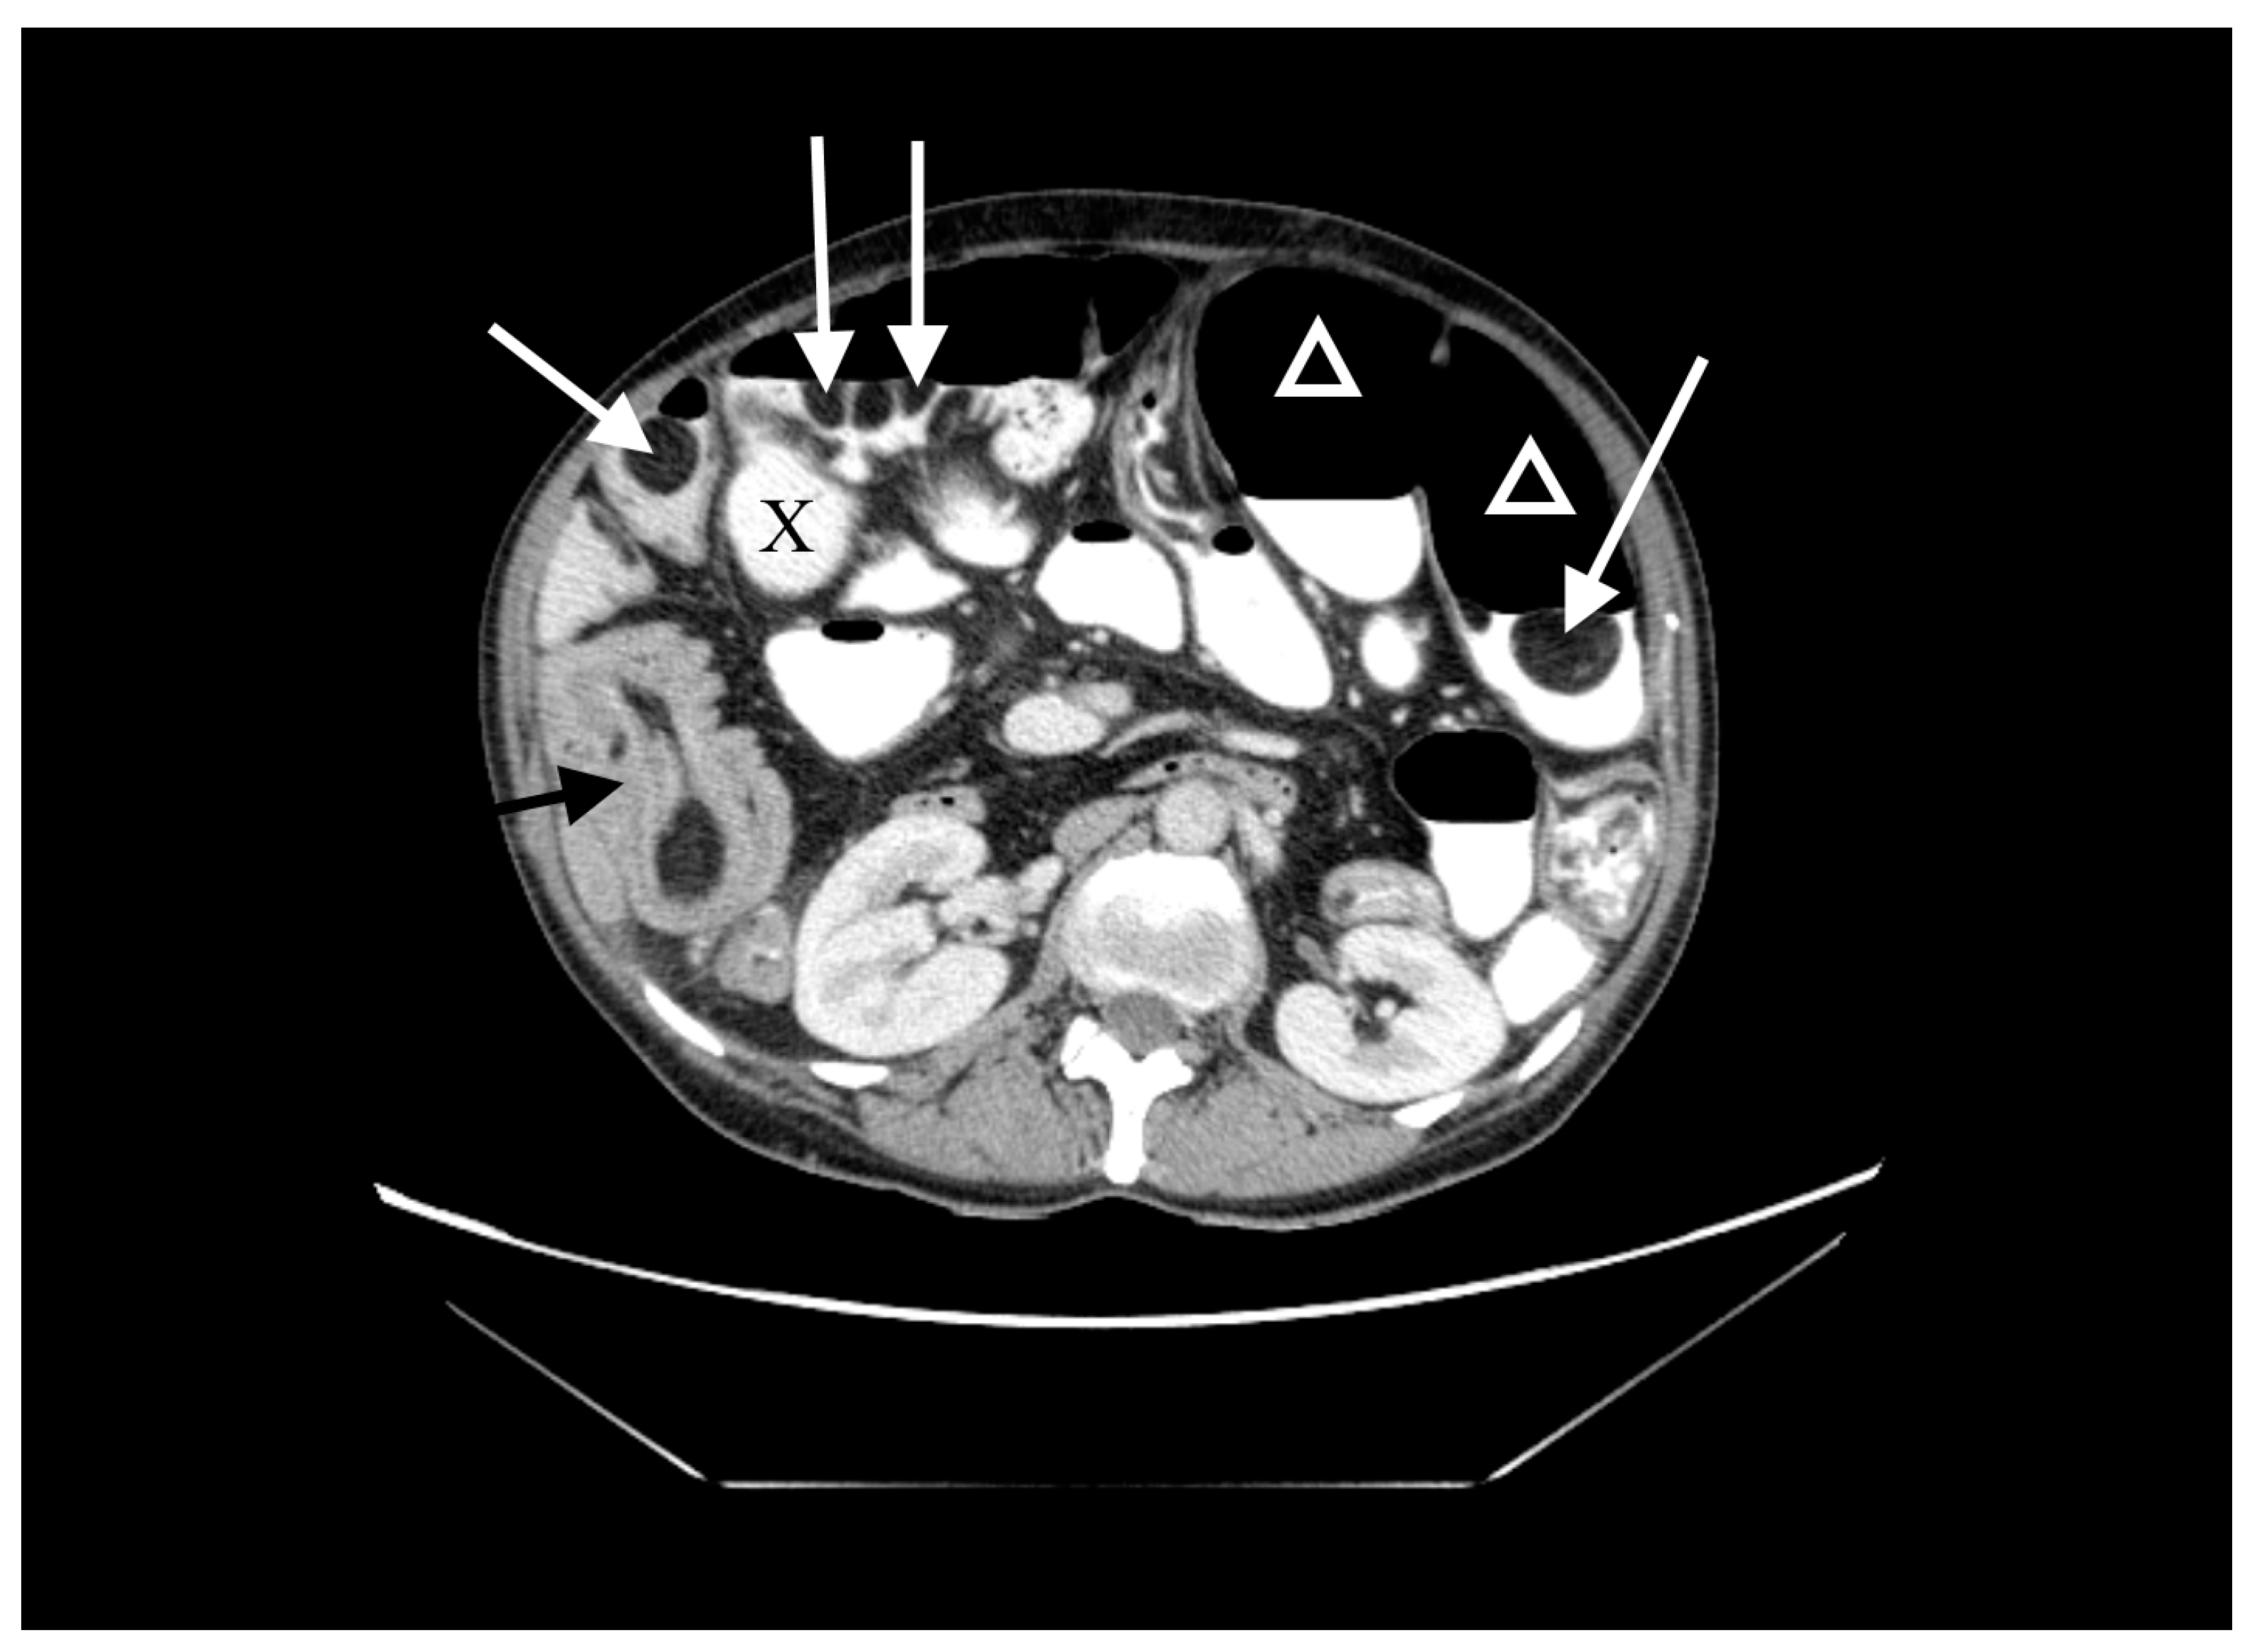

A 60-year-old woman was admitted to the emergency department complaining of acute abdominal pain, vomiting and diarrhea. Her medical history included appendectomy in childhood, hysterectomy, hepatic steatosis, chronic kidney disease (CKD) and chronic malnutrition with iron deficiency. She has also been treated for indeterminate inflammatory bowel disease (she reported taking sulfasalazine, 1.0 g three times daily) and had a twenty-year history of recurrent abdominal pain accompanied by a feeling of fullness and abdominal distension. Twenty-six years prior to admission, she underwent surgery for ileus and a large polyp in the ileum was locally resected. The patient did not provide documentation from her previous hospitalizations in other wards. Physical examination revealed absence of bowel sounds and generalized abdominal tenderness. Laboratory tests showed mild anemia and low serum protein level. Abdominal CT scan demonstrated small bowel distension (Figure 1) with ileo-ileal intussusception caused by one of multiple pedunculated lipomatous polyps arising from the mesenteric border of the jejunum (Figure 1 and Figure 2). Multiple giant diverticula were also visualized (Figure 1 and Figure 3).

Figure 3.

Contrast-enhanced CT image of the abdomen and pelvis, frontal section. Multiple giant diverticula (X).